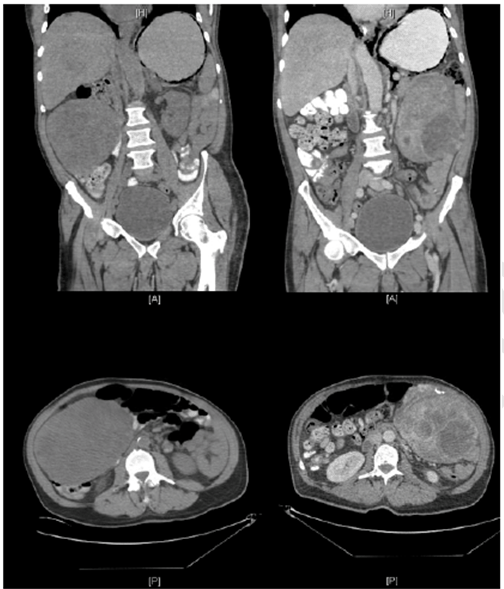

A 60-year-old male with disabling paranoid schizophrenia was sent from his group home to the emergency room after an unwitnessed fall and sustaining a left tibial-fibula comminuted fracture. The patient was admitted to the hospital for medical optimization of his poorly controlled diabetes and hypertension in anticipation of surgical repair. However prior to any intervention, he developed an acute onset of non-bilious emesis and abdominal distention. The patient reported previous such episodes which resolved without any intervention. He denied any abdominal surgery, family history was unknown and his recent screening colonoscopy was normal. On exam, his abdomen was soft, markedly distended but there was no evidence of peritonitis. He was afebrile and hemodynamically stable. His laboratory values were all within normal limits, without evidence of a leukocytosis or acidosis. A bedside abdominal X-ray showed a distended stomach with a paucity of gas in the small bowel and large fecal burden in the colon (Figure 1). In the absence of any previous abdominal surgery, a computed tomography (CT) scan with only oral contrast was obtained. It revealed a 17-cm pedunculated mass compressing the gastric antrum causing marked dilation, however, there was no evidence of pneumatosis. A nasogastric tube was placed for decompression, and the patient obtained a CT scan with oral and intravenous contrast to ascertain the etiology of this mass. This subsequent CT scan revealed the known heterogeneously enhancing solid mass with eccentric calcification with pedicle inseparable from the duodenum/gastric pylorus. However, there was an interval migration of the mass from the right abdomen to the left with possible twisting on the mesentery (Figure 2). There was new gastric pneumatosis as well as new portal venous gas. The decision was made to emergently take the patient to the operating room for an exploratory laparotomy. In the operating room, a midline incision was made to enter the peritoneal cavity and immediately a large well circumscribed mass was visualized in the left lower quadrant. The mass was pedunculated and the broad base originated from the inferior aspect of the liver arising from the lesser omentum. This mobile base draped over the gastric antrum and first part of the duodenum causing the mechanical gastric outlet obstruction (Figure 3). On further exploration, there was no evidence of ascites, lymphadenopathy, or any distal metastasis. The anterior and posterior serosal surfaces of the stomach were carefully inspected and showed no signs of ischemia. The pedicle was suture ligated and divided at the origin and the specimen freely delivered from surrounding structures. This was sent to a regional tertiary referral oncology pathology unit. On gross report the tumor measured 17x15x10.5 cm and weighed 1.5 kg. It was described as having a rubbery to fleshy cut surface and focal cystic areas (Figure 4). Microscopically, the findings were that of a spindle cell sarcoma with large areas of necrosis as well as increased mitotic activity 8-10 MF/10 HPFs. Although the tumor was mostly composed of a monotonous proliferation of spindle cells separated by a prominent fibrous and sclerotic stroma, there were scattered pleomorphic cells throughout. The immunohistochemical stains show the tumor was diffusely positive for CD34, while negative for CD 117, S100, smooth muscle actin (SMA), CD31 and Factor VIII. Based on the clinical presentation, histologic appearance of a spindle cell lesion associated with abundant collagenous stroma and CD34 reactivity, one possibility included a malignant solitary fibrous tumor. In order to confirm this diagnosis further immunostaining for a recurrent gene fusion NAB2-STAT6 was found to be positive, confirming the diagnosis of SFT. The patient was observed and his postoperative course was uneventful. His NGT removed on postoperative day-1. The patient was discharged after he tolerated a regular diet with return of normal bowel function on postoperative day-2. On immediate postoperative and a three-month follow-up visits, he has been without any recurrence of symptoms.

Figure 1: Abdominal X-ray showing markedly dilated stomach.

Figure 2: Computed tomography scan within 24 hours of each other depicting movement of obstructing mass from right abdomen to left.